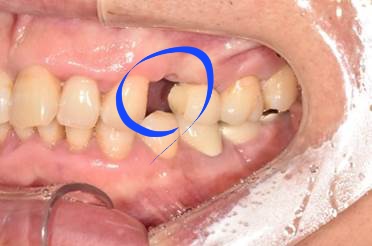

50대 남성분으로 본원에 오시기 2개월 전쯤 식사를 하시던 중 이가 깨지는 사고가 있었습니다.

곧바로 거주지 근처 치과에서 발치만 하시고, 임플란트 시술은 저희 디데이에서 진행하게 되셨는데요.

(전) 2021-09-29

사실 치아를 상실했을 때는 임플란트 시술을 빨리하는 것이 좋습니다.

치아가 없는 빈 공간으로 주변 치아가 옆으로 눕거나 이동하는 증상이 나타날 수 있기 때문입니다.

또한 위아래 치아가 서로 잘 맞물려야 하는데 이가 없다면, 남아있는 치아가 위로 올라가거나 아래로 내려앉는 증상이 생길 수 있어서 주의해야 합니다.

아울러 환자분은 치아가 없어 음식물이 계속 끼고, 말할 때 빈 공간이 보여 큰 불편감을 느끼셨는데요.

최종 보철물을 올리기 전에는 임시치아를 해드리기 때문에 큰 불편감 없이 지내실 수 있습니다.